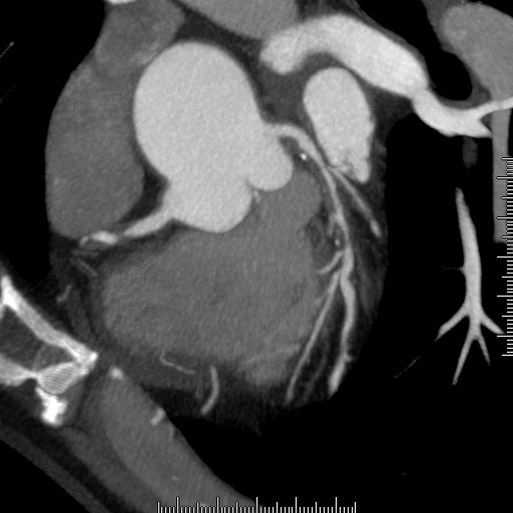

冠状動脈バイパス手術後の経過観

手術後の患者様の経過を下記の通り観察できます。心臓の裏側ももちろん診断可能です。

様々な画像表示処理方法を用い診断します。

ボリュームレンダリング

造影検査画像ビュー